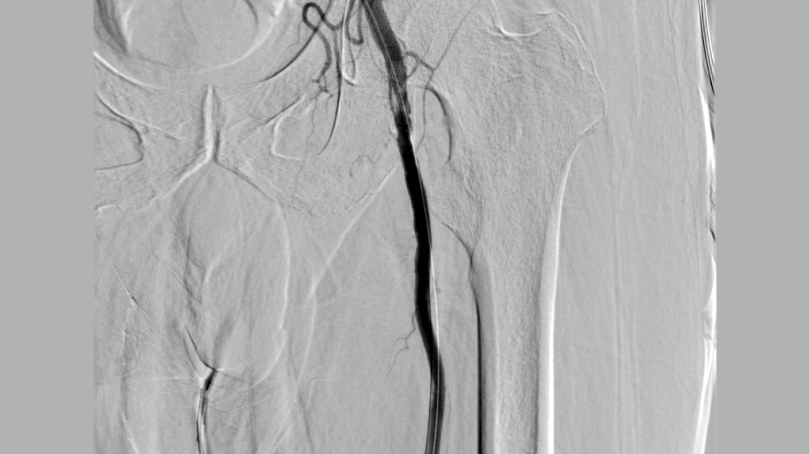

李煒主任帶領團隊通過一個針眼大小的穿刺點,將Rotarex機械血栓抽吸導管精準送達被血栓堵塞的股動脈。隨著設備啟動,大量混合性血栓被粉碎并抽吸出體外,暴露出血管壁原有的狹窄部位。

隨后,對股淺動脈及腘動脈兩處重度狹窄進行切割球囊擴張,血流瞬間恢復通暢。整個手術歷時約2小時,術中造影顯示:堵塞血管全程開通,左下肢血運重建成功。